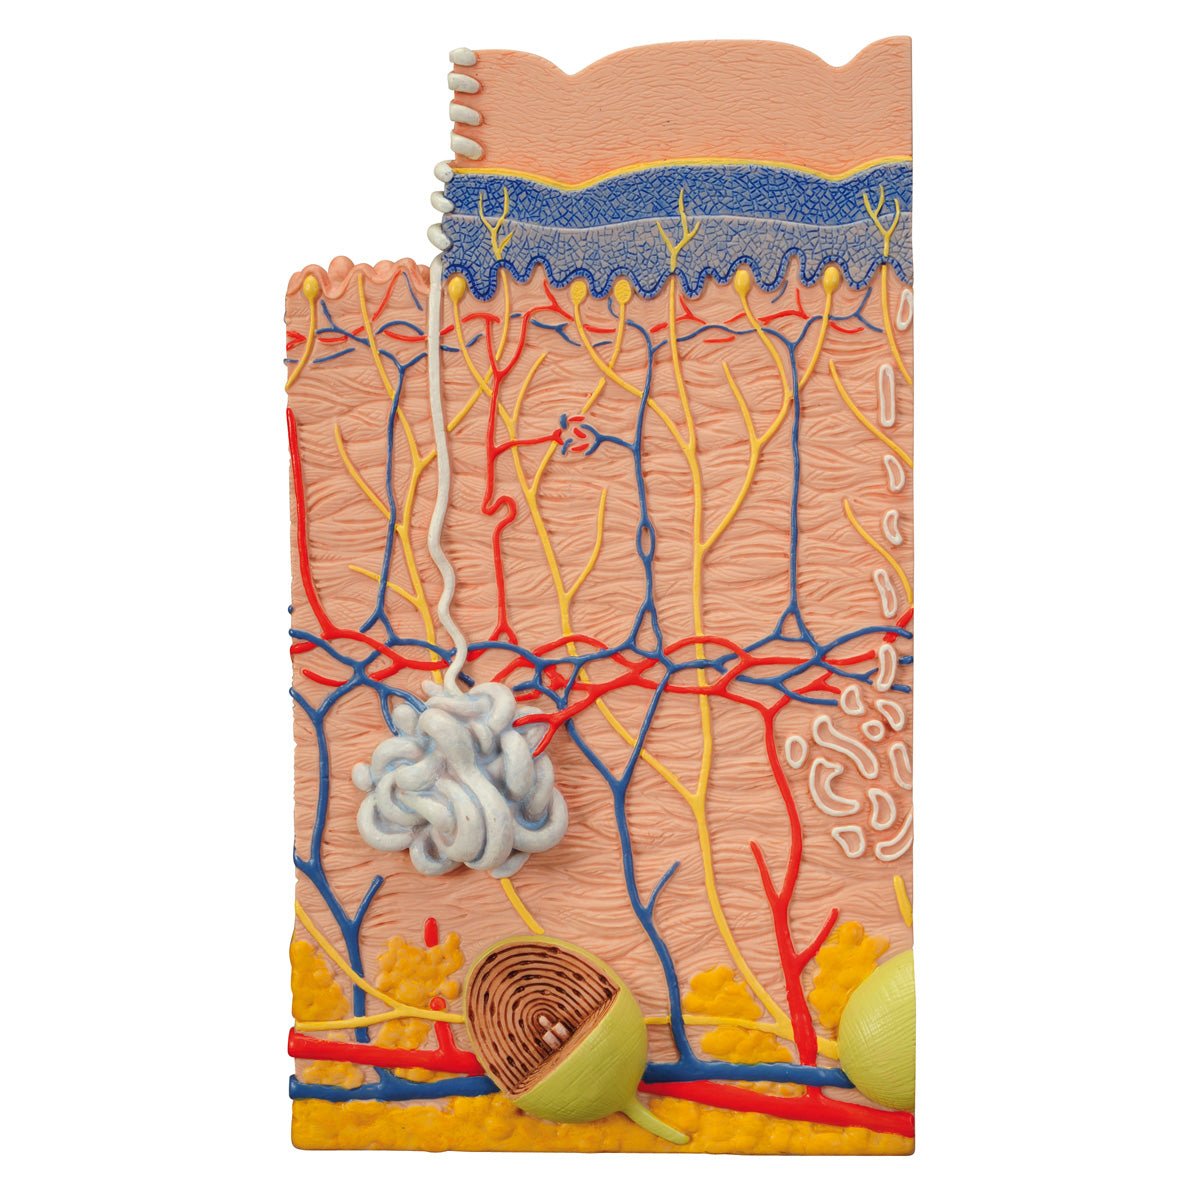

Salg af anatomiske modeller er det bærende element i eAnatomi, selvom vi også bruger mange ressourcer på at udvikle vores egne anatomiske materialer som fx plakater. Anatomiske modeller anvendes til forskellige formål og kan både vise afgrænset væv, organer samt organsystemer. Søger du en simpel model af knoglevæv eller måske en avanceret torso-model baseret på MRI teknologi, kan du finde det hele på eanatomi.com.